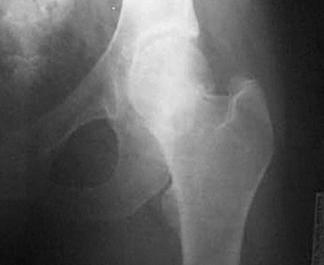

Luxatie de sold stang Luxatie de sold stang

Fractura

de cap femural Fractura de cap femural

de cap femural Fractura subcapitala cu usoara deplasare

Fractura intertrohanteriana multifragmentara Luxatie de patela